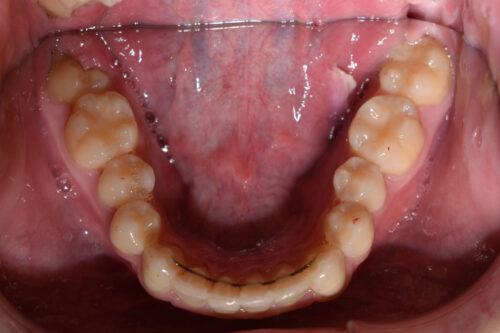

歯のがたつき(叢生)が強く認められ

また下の歯が 全く見えず 過蓋咬合の状態でした。

非抜歯矯正治療で

ワイヤー矯正治療を開始いたしました。